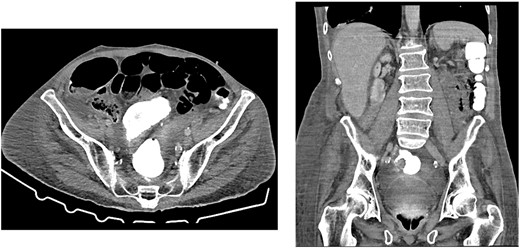

Axial CT showing tension pneumoperitoneum and collapsed inferior vena cava (arrow)

On presentation, his temperature was 37.8°C, and he was hypotensive at 100/45 mmHg and tachypneic with a respiratory rate of 22. He was in moderate respiratory distress and was placed on 2 L oxygen via nasal prongs. On abdominal examination, mild distension was noted with lower abdominal tenderness with rebound tenderness and guarding in the right lower quadrant. He had normal leukocytes of 5 × 109 /L (N: 4.0–11 × 109/L) and lactate was normal at 1.6 mmol/L (N: 0.5–2.2 mmol/L). X-ray chest showed free air under the diaphragm suggestive of pneumoperitoneum (Fig. 1). A CT abdomen was performed showing large-volume free air suggestive of a viscous perforation and moderate volume of free fluid in the abdomen (Fig. 2). The site of perforation was not confidently established on the study. There was generalized oedema of the right side of the colon with multiple loops of dilated small bowel. His Physiological and Operative Severity Score for enumeration of Mortality and Morbidity (POSSUM) score would be 81% predicted mortality and 98.8% predicted morbidity if he were to undergo an emergent laparotomy operation. Family discussion was made, and he decided not to proceed with operative management. He was managed conservatively with piperacillin-tazobactam and decompressed with nasogastric tube insertion. As the days progressed, his abdomen became increasingly distended and tympanic, but not peritonitic. We repeated a CT chest and abdomen three days after initial admission and it was reported he had tension pneumoperitoneum (Fig. 3). CT with oral contrast was also performed to exclude an upper GI perforation.

Here, we present a case of spontaneous idiopathic pneumoperitoneum with CT findings of tension pneumoperitoneum managed successfully with bedside decompression using a pig-tail catheter attached to a chest drain. Failure of decompressing the tension pneumoperitoneum may result in hemodynamic instability and ischemia of abdominal organs as large pneumoperitoneum may compress on the inferior vena cava reducing venous return to the heart. CT findings of tension pneumoperitoneum include marked elevation of diaphragm, decreased thoracic volume and/or compression of the inferior vena cava [10]. Emergency percutaneous needle compression using 16G cannulas have been used in cases for immediate decompression of the tension pneumoperitoneum [11]. Our patient had a high POSSUM score; for him to undergo a laparotomy would place him at a high mortality and morbidity risk. Here we demonstrate successful management of idiopathic tension pneumoperitoneum with pig-tail catheter attached to an intercostal drain.